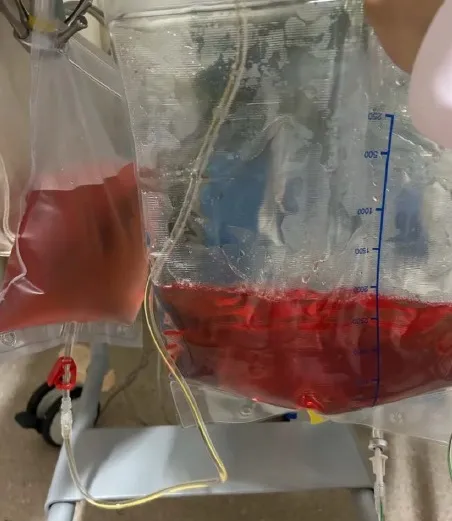

Você já viu um efluente de diálise vermelho? U0001F6A8 Neste caso surpreendente, a coloração da bolsa ajudou a confirmar um diagnóstico crítico. Saiba como diferenciar causas, conduzir o caso e evitar armadilhas diagnósticas.

Valkercyo Feitosa

13 meses atrás